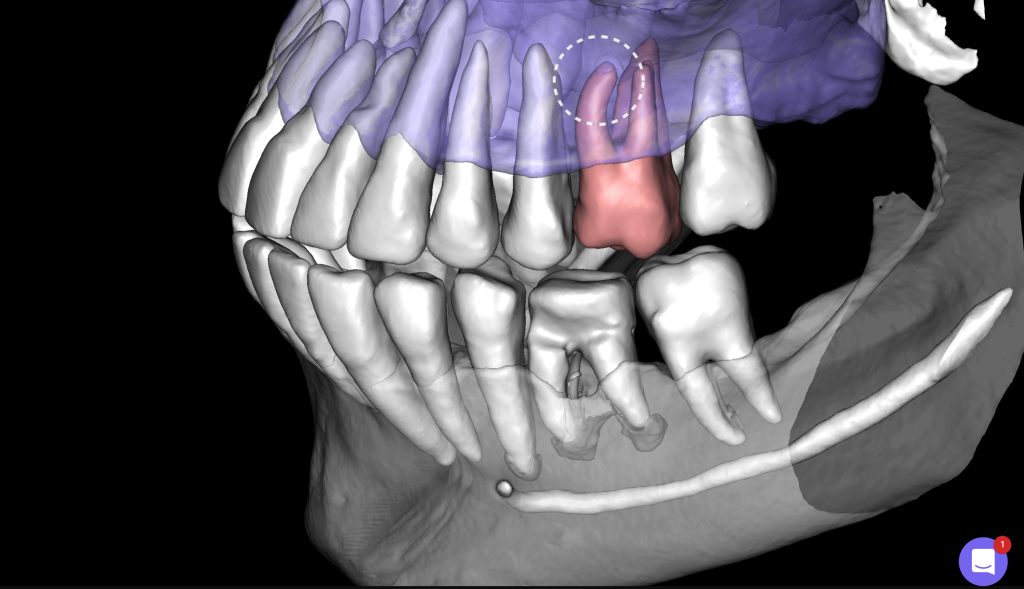

Diagnocat AI helps us to see not only the consequences, but also the causes of the pathology. For example, in this clinical case – the missed MB2 during previous endodontic treatment of tooth 26 (Universal 14)

The 3D-Viewer allows the clinician to align the axes according to the area of interest and to study root canal morphology and anatomy before starting a treatment